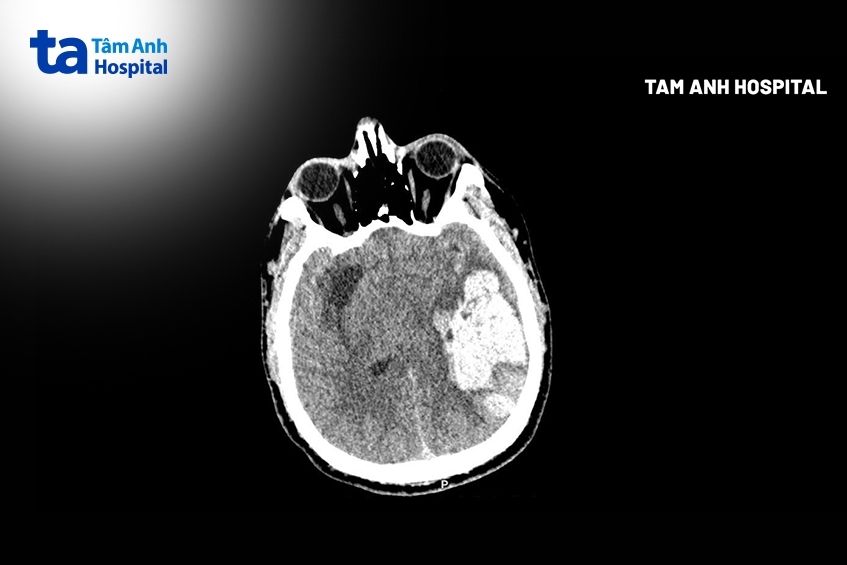

Kết quả chụp CT cho thấy bệnh nhân có ổ tụ máu nhu mô não thùy thái dương đỉnh trái kích thước 40×45×81 mm, chèn ép não thất cùng bên, lệch đường giữa 7 mm sang phải, thoát vị hồi hải mã trái (một phần hồi hải mã ở thùy thái dương trái bị đẩy lệch xuống dưới và vào trong, chui qua dưới liềm đại não).

Sau 30 ngày, sức khỏe anh Đức ổn định, vết mổ hết phù, tri giác cải thiện, giao tiếp được bằng mắt, chức năng vận động dần hồi phục. Kết quả chụp CT kiểm tra cho thấy khối máu tụ đã được lấy sạch, đường giữa trở lại bình thường, não thất chỉ còn ép nhẹ. Hiện người bệnh tiếp tục điều trị phục hồi chức năng với bài tập thiết kế riêng.